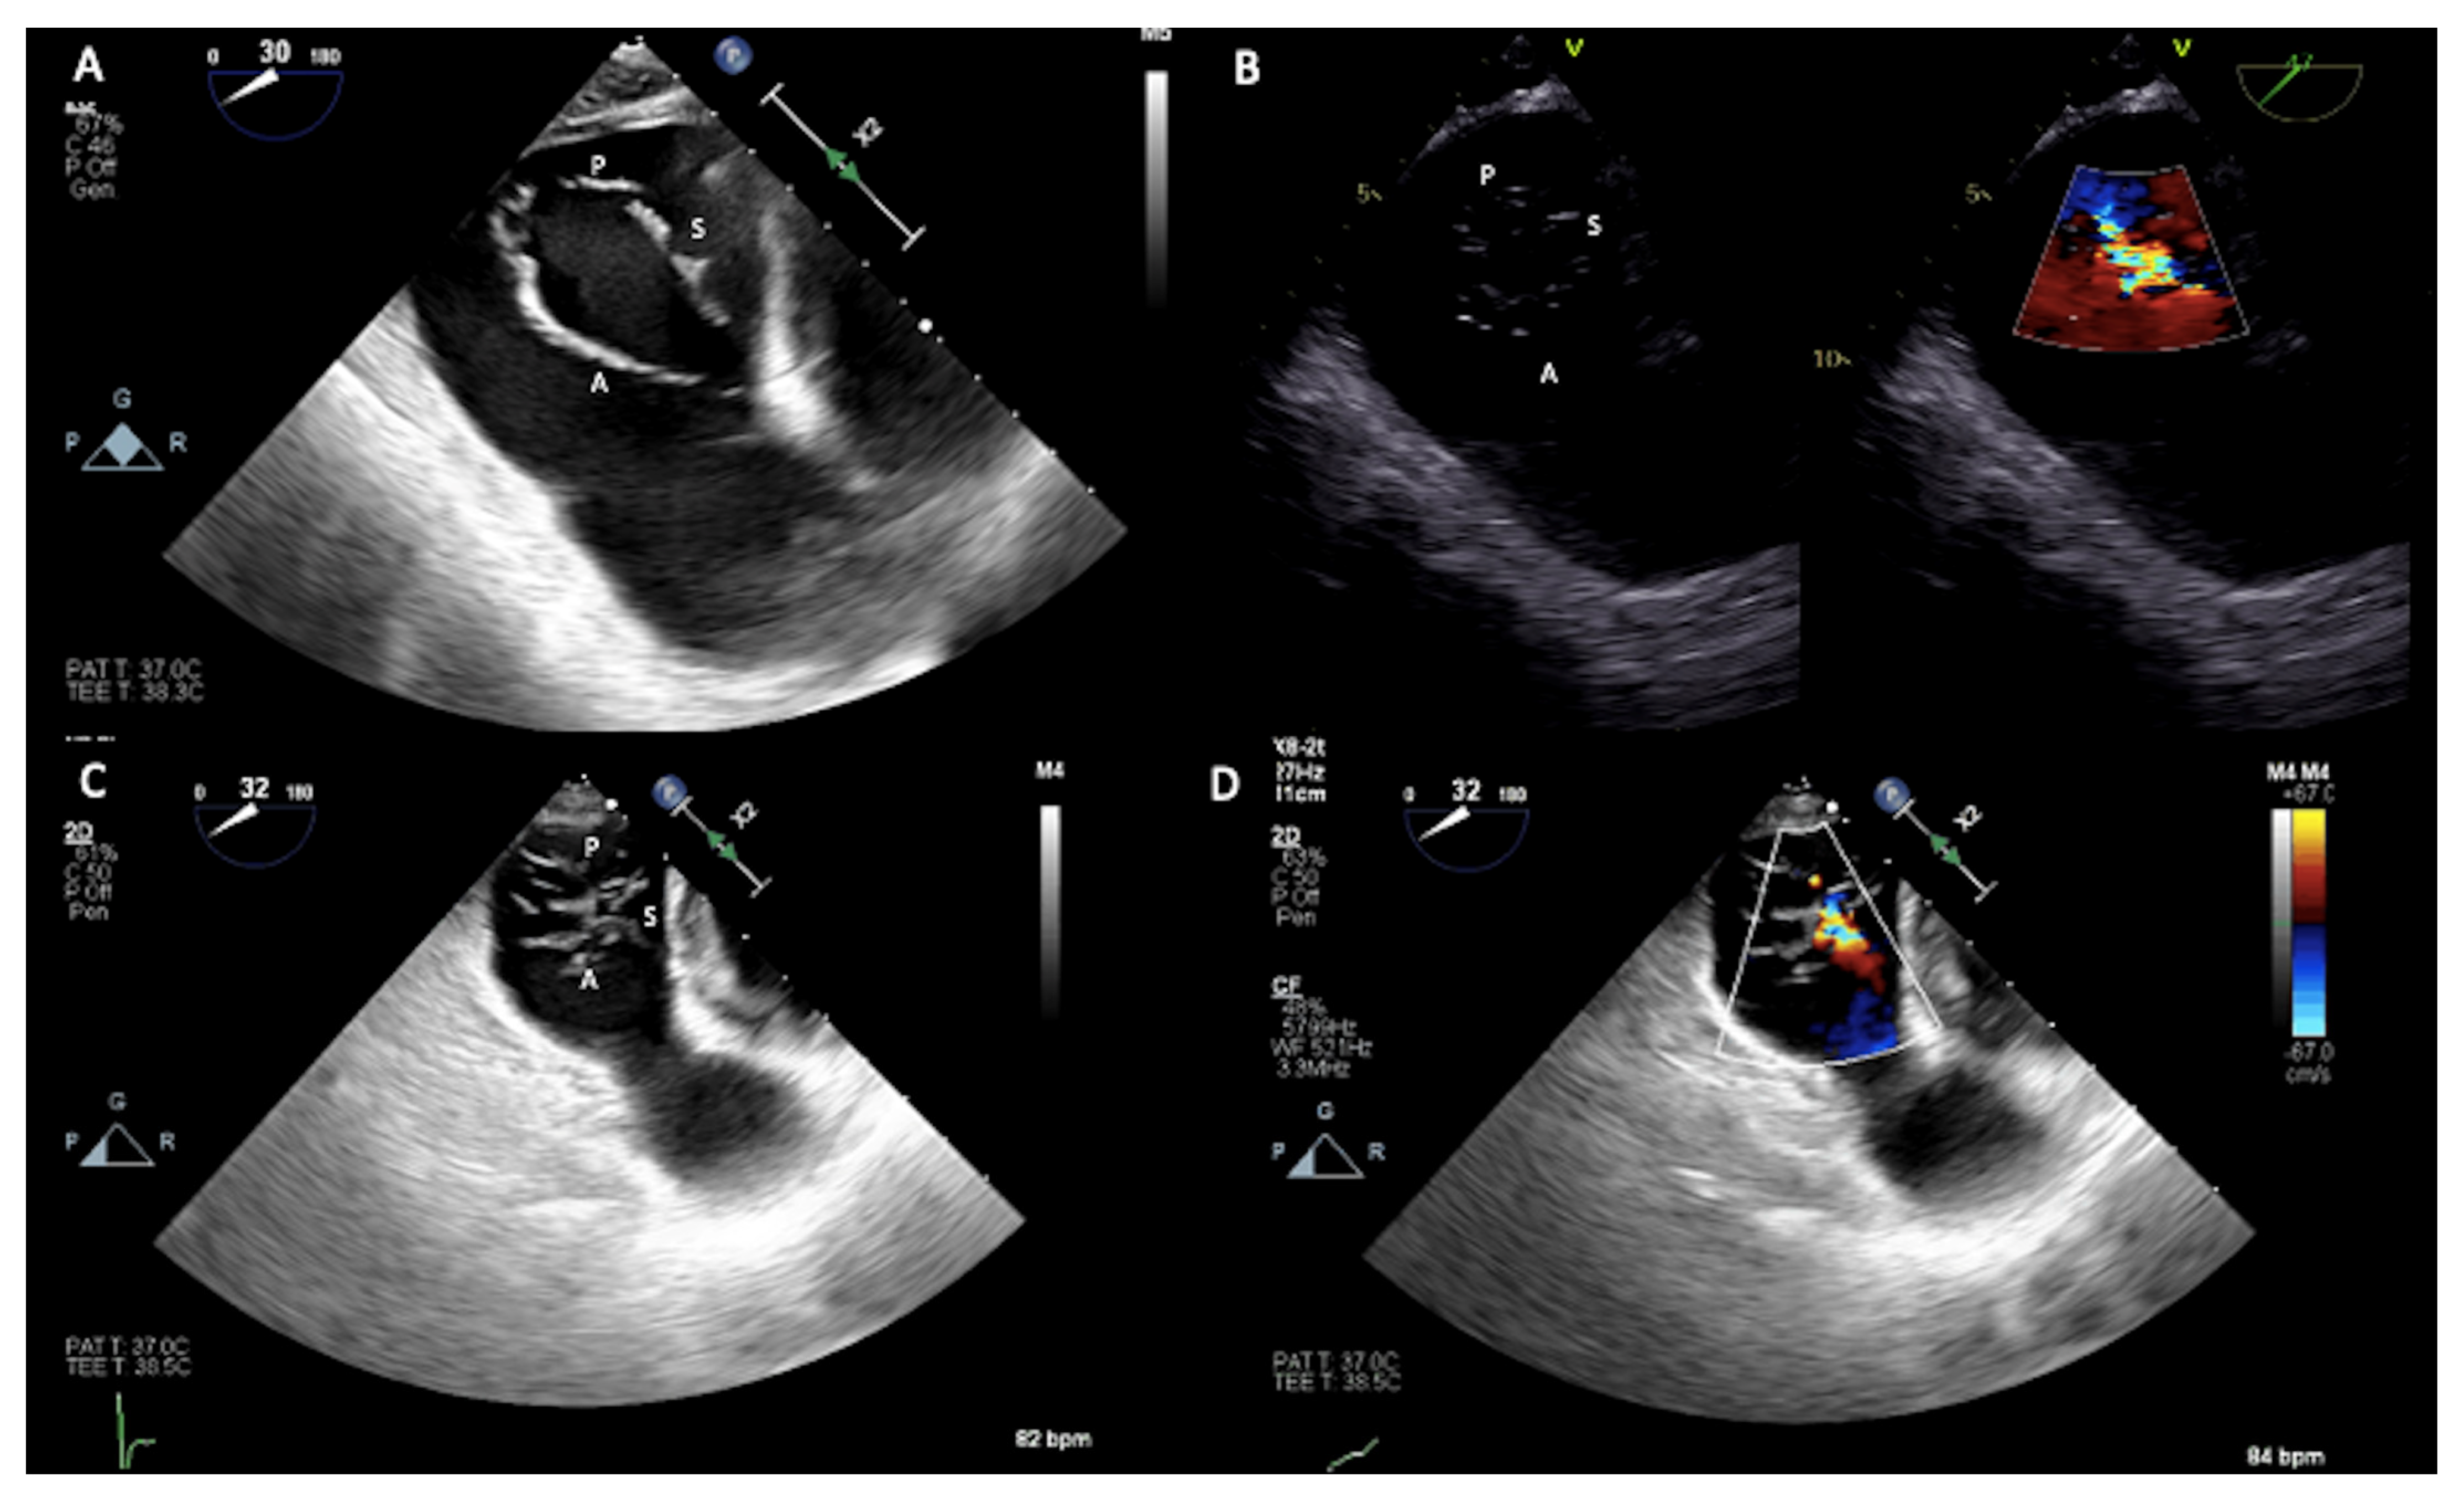

- Sugiura, A.; Tanaka, T.; Kavsur, R.; Oeztuerk, C.; Vogelhuber, J.; Wilde, N.; Becher, M.U.; Zimmer, S.; Nickenig, G.; Weber, M. Leaflet Configuration and Residual Tricuspid Regurgitation after Transcatheter Edge-to-Edge Tricuspid Repair. JACC Cardiovasc. Interv. 2021, 14, 2260–2270. [Google Scholar] [CrossRef] [PubMed]

- Carpenito, M.; Cammalleri, V.; Vitez, L.; De Filippis, A.; Nobile, E.; Bono, M.C.; Mega, S.; Bunc, M.; Grigioni, F.; Ussia, G.P. Edge-to-Edge Repair for Tricuspid Valve Regurgitation. Preliminary Echo-Data and Clinical Implications from the Tricuspid Regurgitation IMAging (TRIMA) Study. J. Clin. Med. 2022, 11, 5609. [Google Scholar] [CrossRef]

- Ancona, F.; Stella, S.; Taramasso, M.; Marini, C.; Latib, A.; Denti, P.; Grigioni, F.; Enriquez-Sarano, M.; Alfieri, O.; Colombo, A.; et al. Multimodality imaging of the tricuspid valve with implication for percutaneous repair approaches. Heart 2017, 103, 1073–1081. [Google Scholar] [CrossRef] [PubMed]

- Agricola, E.; Ancona, F.; Stella, S.; Rosa, I.; Marini, C.; Spartera, M.; Denti, P.; Margonato, A.; Hahn, R.T.; Alfieri, O.; et al. Use of Echocardiography for Guiding Percutaneous Tricuspid Valve Procedures. JACC Cardiovasc. Imaging 2017, 10, 1194–1198. [Google Scholar] [CrossRef]